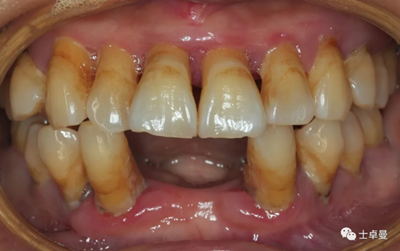

口內(nèi)檢查

臨床檢查:17、37、32-42、37缺失;

前牙區(qū)牙齒扇形移位,口腔衛(wèi)生狀況較差;

菌斑指數(shù):2;

牙石指數(shù):3,色素 (+);

牙齦顏色暗紅,腫脹,質(zhì)地松軟;

口內(nèi)余留牙松動度II°~III°;

根分叉病變III°~IV°。